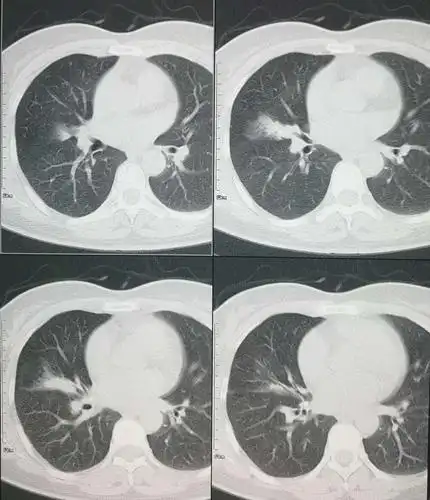

肺科视界:右肺中叶综合征

右肺中叶综合征的鉴别诊断

右肺中叶改变

但是两个不同的病,右上肺大的,这个是一个结核瘤,右肺中叶这个小一点